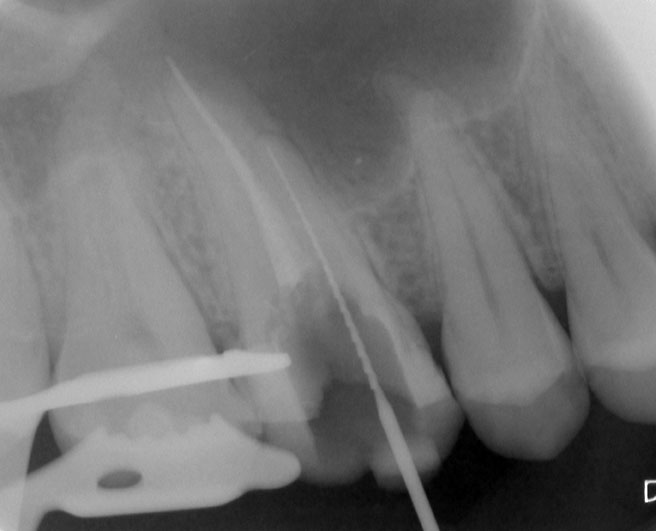

Patient N.M. wünscht eine Drittmeinung, zwischenzeitlich hatte er bereits einen zweiten Zahnarzt konsultiert. Dieser bestätigte eine insuffiziente Wurzelfüllung und vermutete eine Instrumentenfraktur im mb1 (Abb. 1).

Mittels Röntgenaufnahme lässt sich ein frakturiertes Instrument in mb1 vermuten. Des Weiteren scheint es, als sei der distale Wurzelkanal sowie der mb2 nicht abgefüllt worden, was sich zu einem späteren Zeitpunkt der Behandlung bestätigen sollte. Der Patient wurde vom vorbehandelnden Zahnarzt über die Fraktur nicht aufgeklärt.